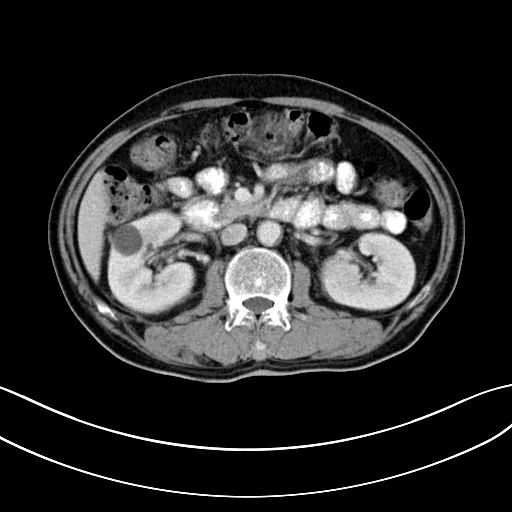

2018.07.04

冷冻治疗手术中

自2017年做冷冻消融术后,安图叔叔两年多时间肿瘤不仅没有增长并多次检查没有复发迹象。安图叔叔认为,冷冻给他带来新的希望,又一次看到复大创造新的奇迹。